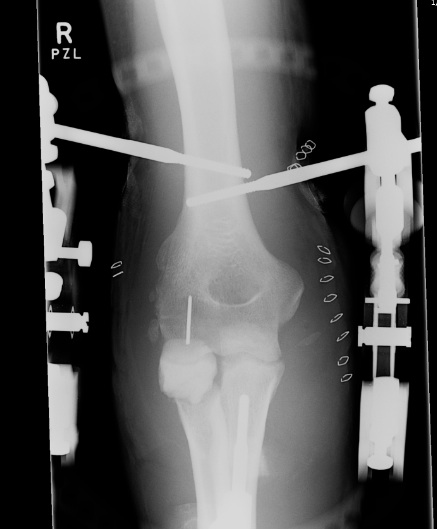

AO surgery reference fixed external fixation

| Lateral humeral pin | Ulna pins |

|---|---|

|

Anterior to radial nerve

Subcutaneous border of ulna

Hinged external fixation

Distal humeral axis

- confirm center of rotation on lateral

- protect ulna nerve

- place guide wire in center of rotation

AO surgery reference hinged external fixator

| Lateral humeral pin | Medial humeral pin | Ulna pins |

|---|---|---|

Anterior to radial nerve |

Posterior to ulna nerve |